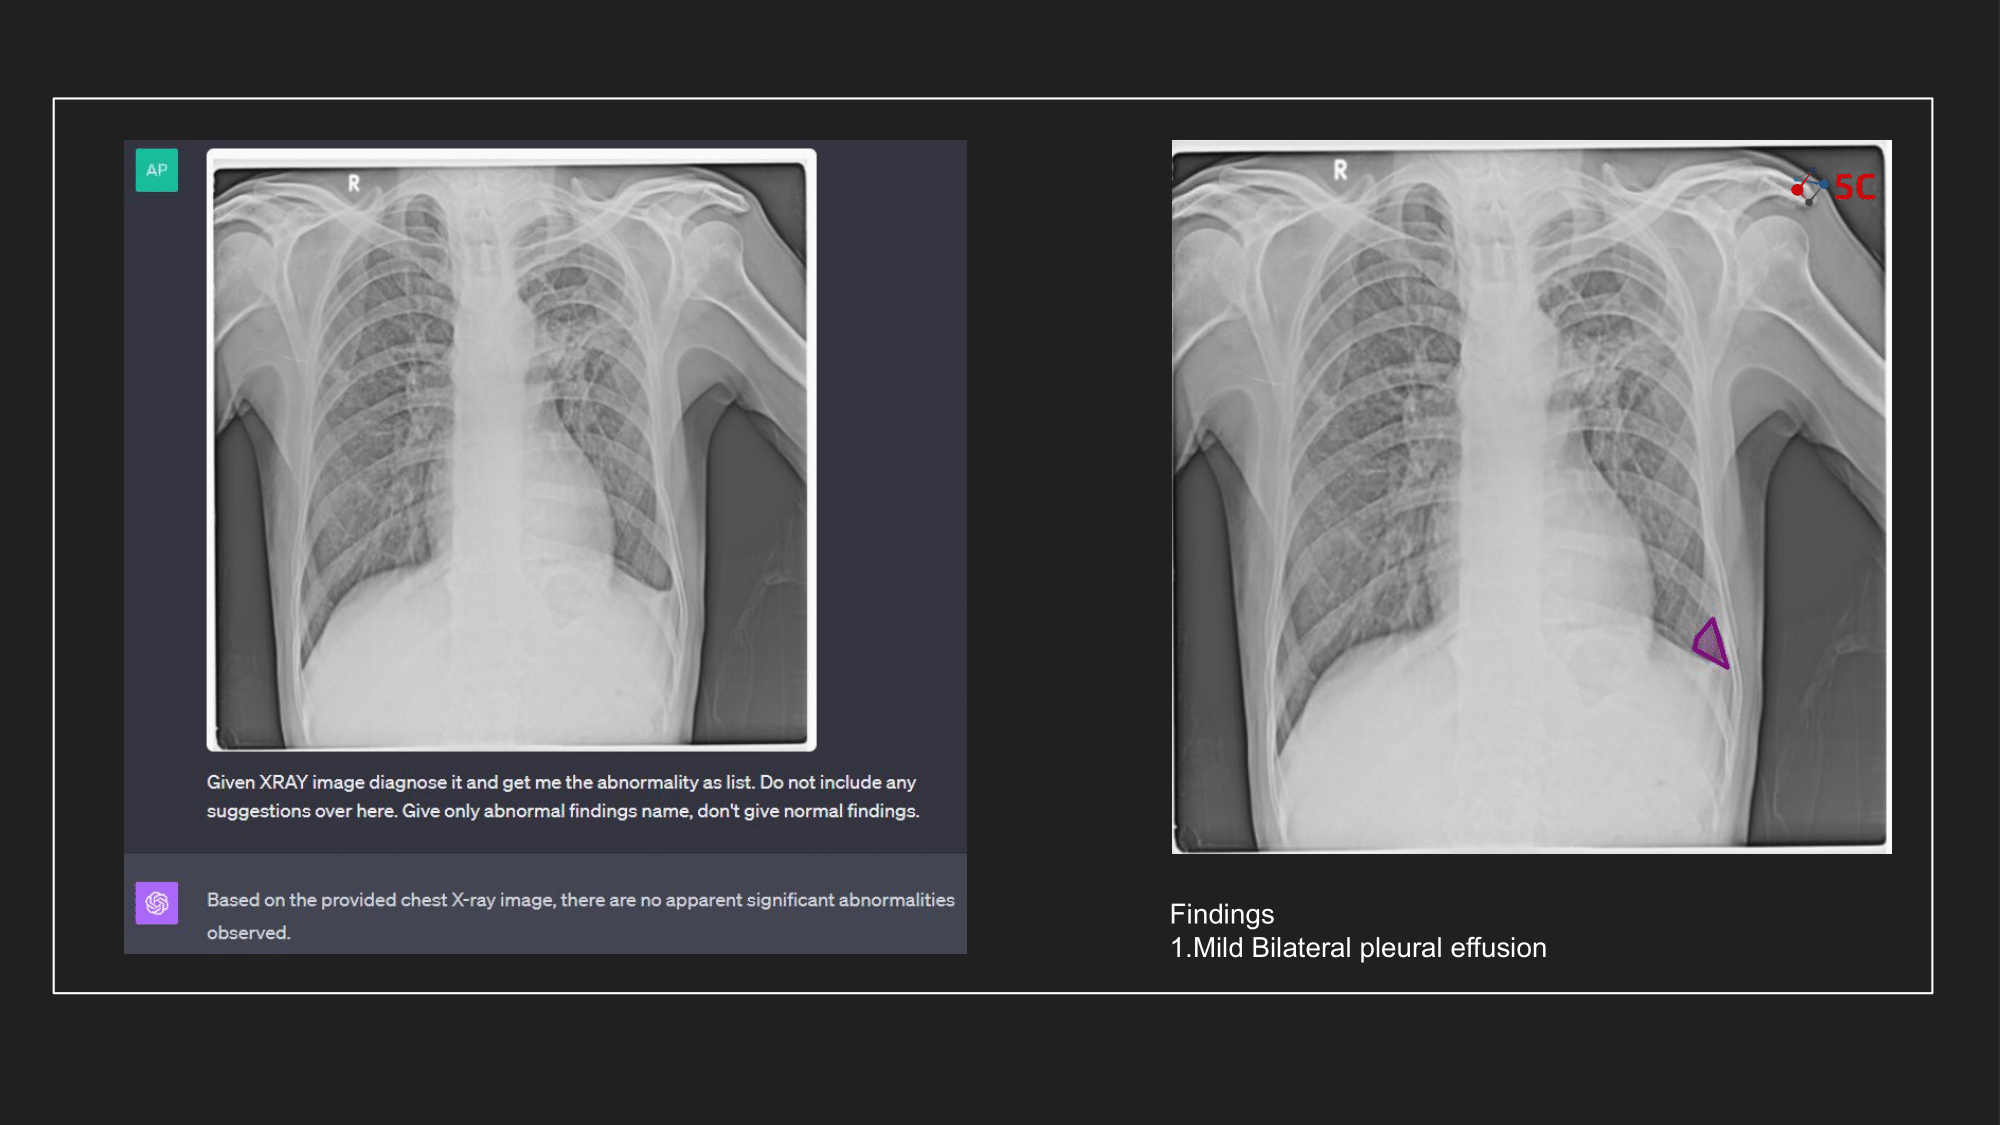

To gauge GPT-4V's prowess in detecting pleural effusion, an experiment was conducted with 10 random chest X-rays known to have pleural effusion. The XRays were sent to GPT-4V, Radiologists as well as to 5C's AI.

Presented below are the results from the experiment.

The output from GPT-4V and from 5C's AI model for the Chest XRays are provided at the end of the post.

At 5C, we are massive believers in the transformative potential of AI in radiology, and our conclusion is that our experiment with GPT-4V and the above radiology images underscores the importance of specialized models. The experiment highlighted that despite GPT-4V's prowess in other domains, it might not yet be primed for radiological applications. That being said, vision transformers as a technology are going to be a key tool in the computer vision stack for AI engineers.

GPT-4V can surely help you fix your bicycle seat, but diagnosing your radiology scan? Not yet, atleast.